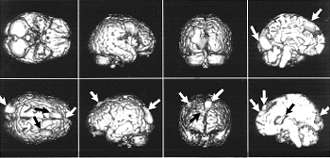

Интересные результаты даёт такой эксперимент. Испытуемому рассказывают одновременно две разные истории: в левое ухо одну, в правое — другую. На верхнем фото изображены разные проекции мозга — стрелками отмечены активизированные зоны, когда внимание сосредоточено на истории, рассказываемой в левое ухо. Внимание испытуемого „переключилось“ на „историю в правом ухе“ (нижнее фото). Можно заметить, что для фиксации внимания на „историю в правом ухе“ требуется гораздо меньшая активность мозга. Это связано с праворукостью большинства людей — обычно они берут телефонную трубку правой рукой и прикладывают её к правому уху. |

Кроме непроизвольного внимания есть ещё и селективное. Это так называемое „внимание на приёме“, когда все вокруг говорят разом, а вы следите только за собеседником, не обращая внимания на неинтересную вам болтовню соседа справа. Во время эксперимента испытуемому рассказывают истории: в одно ухо — одну, в другое — другую. Мы следим за реакцией на историю то в правом ухе, то в левом и видим на экране, как радикально меняется активизация областей мозга. При этом активизация нервных клеток на историю в правом ухе значительно меньше — потому, что большинство людей берут телефонную трубку в правую руку и прикладывают её к правому уху. Им следить за историей в правом ухе проще, нужно меньше напрягаться, мозг возбуждается меньше.